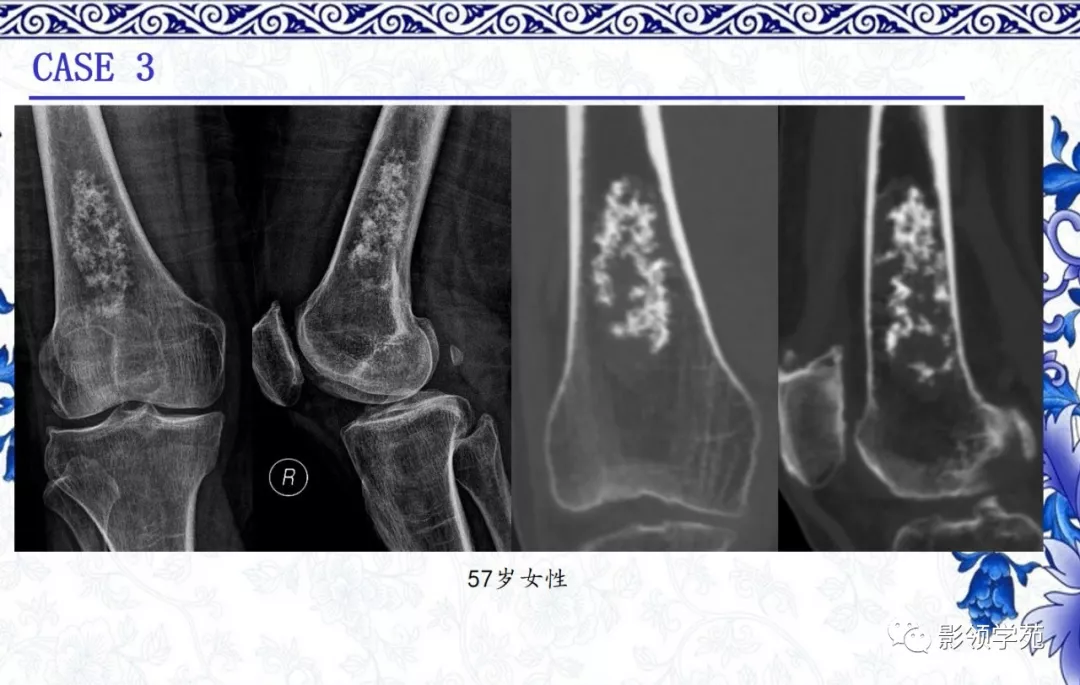

内生软骨瘤

· 良性肿瘤

· 多见于10-50岁

· 最常见于手部短管骨,长管骨多见于肱骨近端、胫骨远端、股骨近端及远端髓腔内

· 影像表现:

1. 多呈分叶状,边界清楚,缺乏硬化

2. 钙化程度不一,呈典型的点状、环状和弧形

3.中心型居多,可见膨胀或骨内膜扇贝样改变

4.非矿化区密度近似水,T2WI高信号,可见低信号钙化及分隔